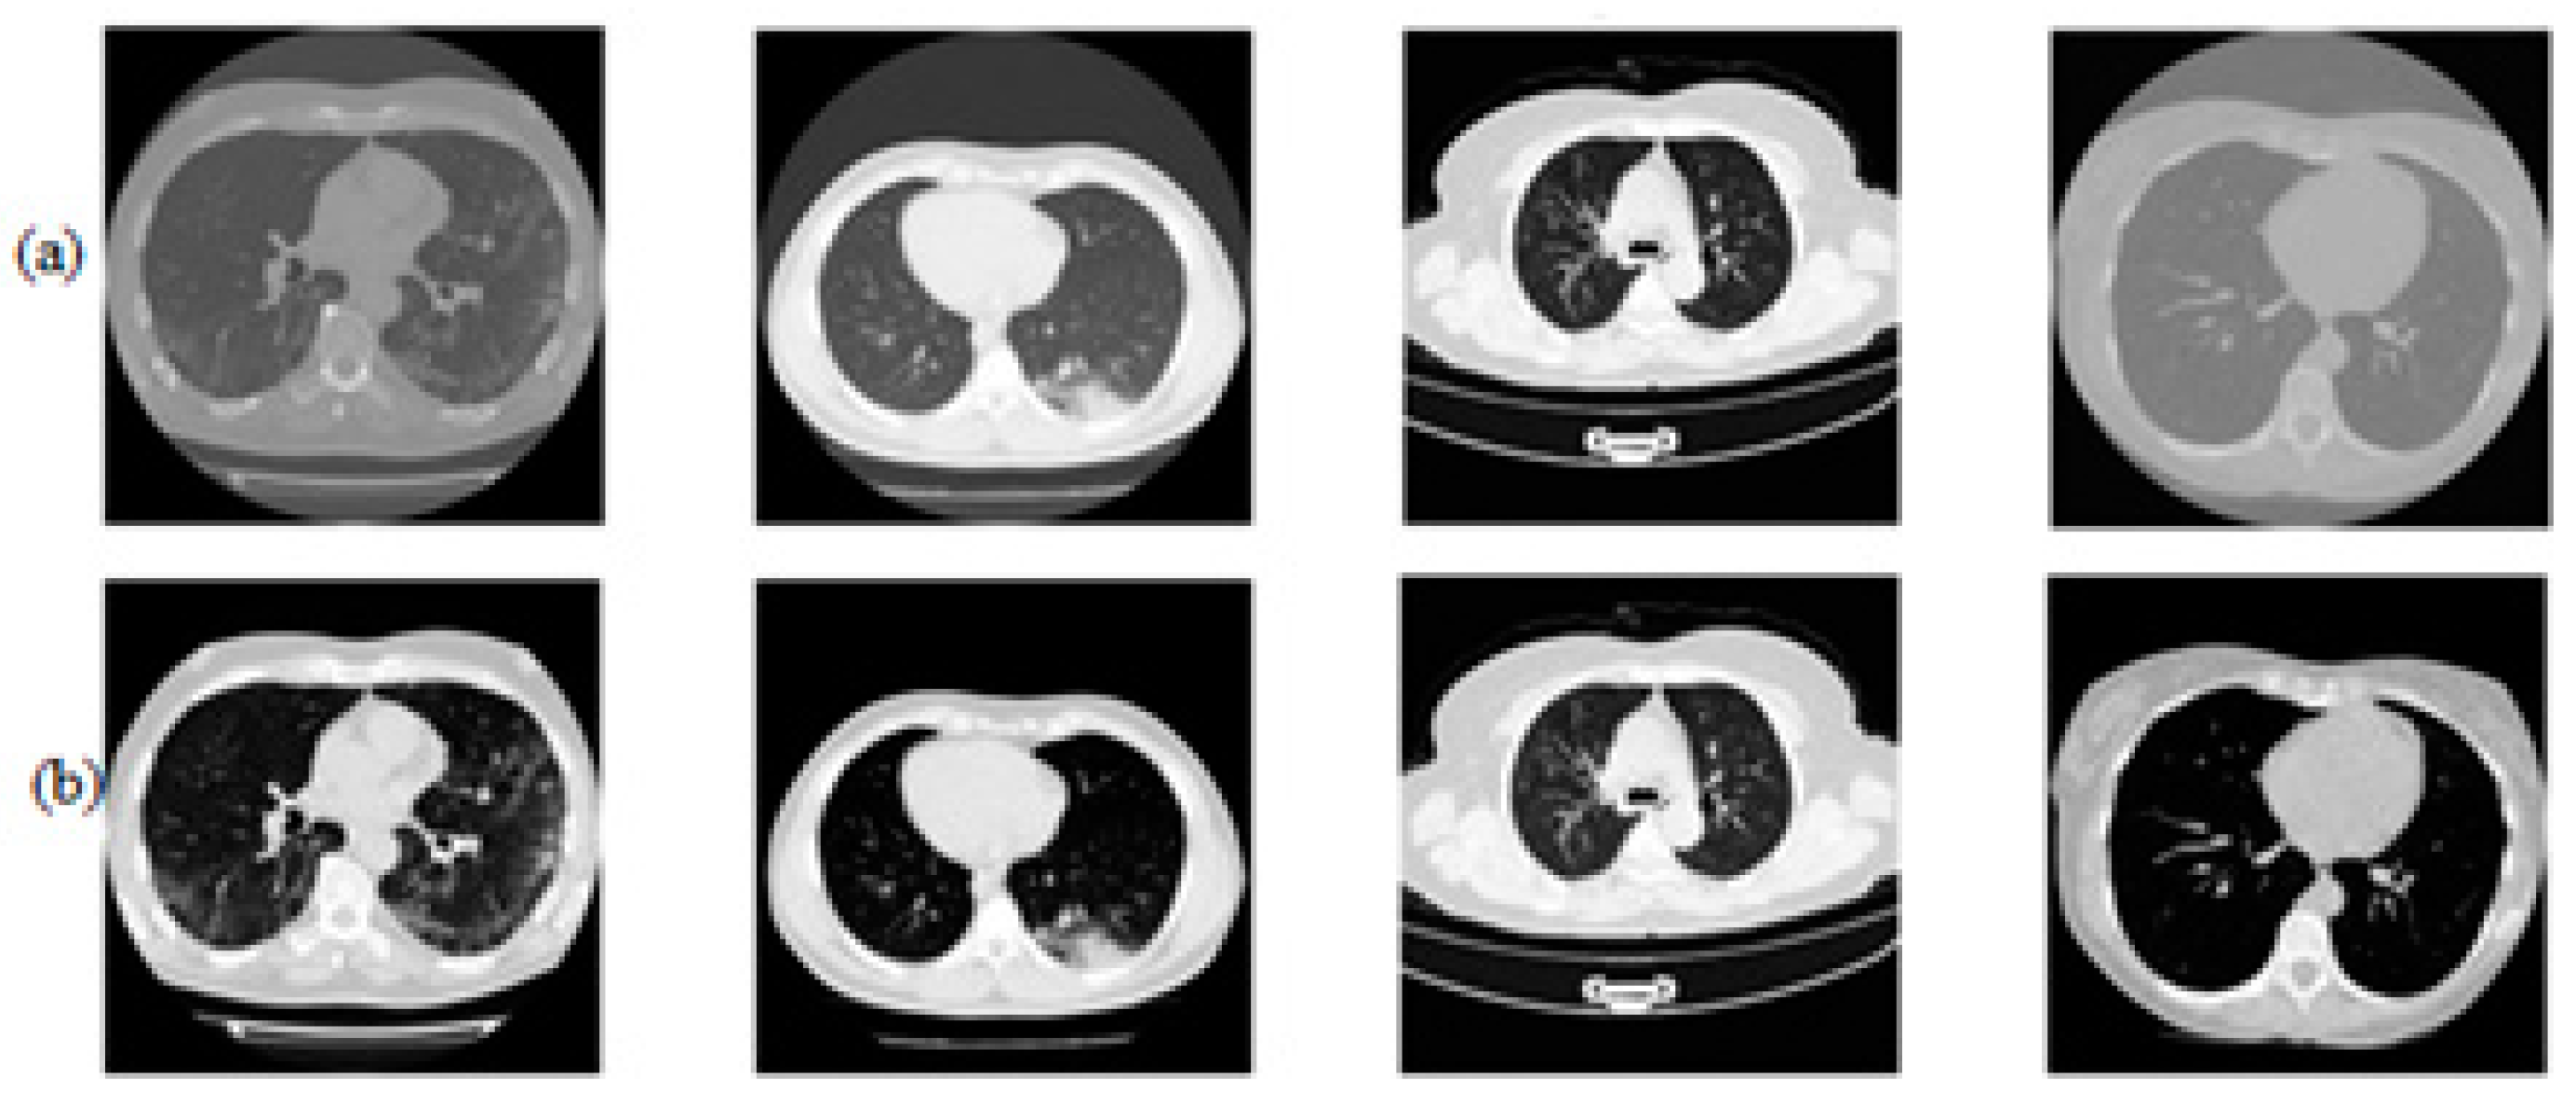

2.2. Data Pre-Processing

2.2.1. Enhanced CNN